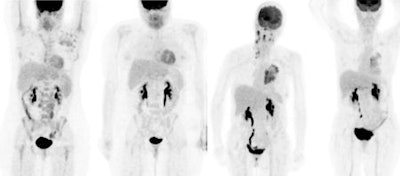

For this year's award, Wagner chose a pair of images that demonstrate the use of radiotherapeutic payloads attached to chemotherapy drugs that illustrate the evolving discipline of radioimmunotherapy. The images came from a study performed at Stanford University in Stanford, CA, that treated non-Hodgkin's lymphoma patients with two types of radioimmunotherapy agents, one with an iodine-131 payload attached to the tositumomab (Bexxar) chemotherapy agent, and another that used yttrium-90 attached to ibritumomab tiuxetan (Zevalin).

| These images demonstrate the use of yttrium-90-labeled ibritumomab tiuxetan (Zevalin) and iodine-131-labeled tositumomab (Bexxar) in a pair of non-Hodgkin's lymphoma patients. Two images at far left are before and after Zevalin-based radioimmunotherapy; images at right are before and after Bexxar-based radioimmunotherapy. Images courtesy of SNM. |

The Image of the Year award is actually going to two studies that show PET exams conducted on two patients, neither of whom demonstrated any metabolically active non-Hodgkin's lymphoma three months after treatment with the radioimmunotherapy agents, Wagner said. The images came from a larger study of 71 patients, 35 of whom received radiolabeled Bexxar and 36 of whom received radiolabeled Zevalin.

Of the Bexxar group, 24 of 35 patients responded to the treatment, while 28 of 36 Zevalin patients responded to that therapy. Between the two groups, 27 showed complete response to the drug; however, radioimmunotherapy wasn't effective in 19 of the 71 patients.